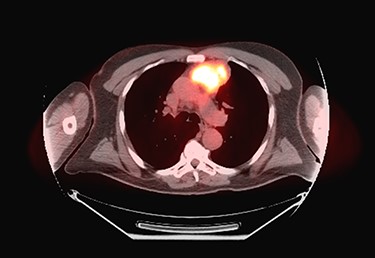

Sixty-three-year-old male was with the history of diabetes and hypertension who presented with 2 days of new onset, intermittent and non-pleuritic left-sided chest pain, with a few months of new onset exertional dyspnea. Chest X-ray showed a convex shaped mass at the left hilum. Chest CT angiography revealed a 5.6 × 7.1 × 5.4 cm hypodense mass in the anterior mediastinum involving the adjacent anterior medial left upper lobe, and adjacent mildly enlarged aorticopulmonary window lymph nodes (Fig. 1). PET scan demonstrated a hypermetabolic anterior mediastinal mass adjacent to medial left upper lobe highly suggestive of malignancy (Fig. 2). Ultrasound-guided core needle biopsy showed nests of small cells with peripheral palisading and focal abrupt transition to squamous cell, consistent with basaloid carcinoma of thymic gland. Immunostainings of the tumor cells were positive for cytokeratin AE1/AE3, cytokeratin CK904, p63 and p40.

Pre-operative PET scan demonstrating a hypermetabolic anterior mediastinal mass.